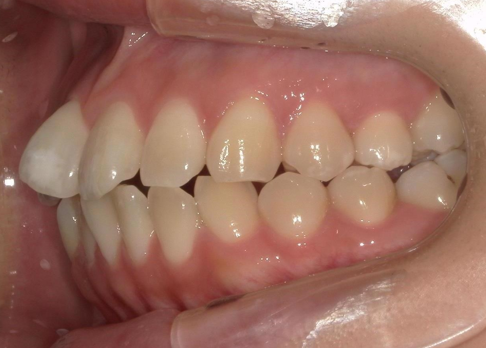

年齢 20代女性

主訴

上顎前突

前歯叢生

BEFORE